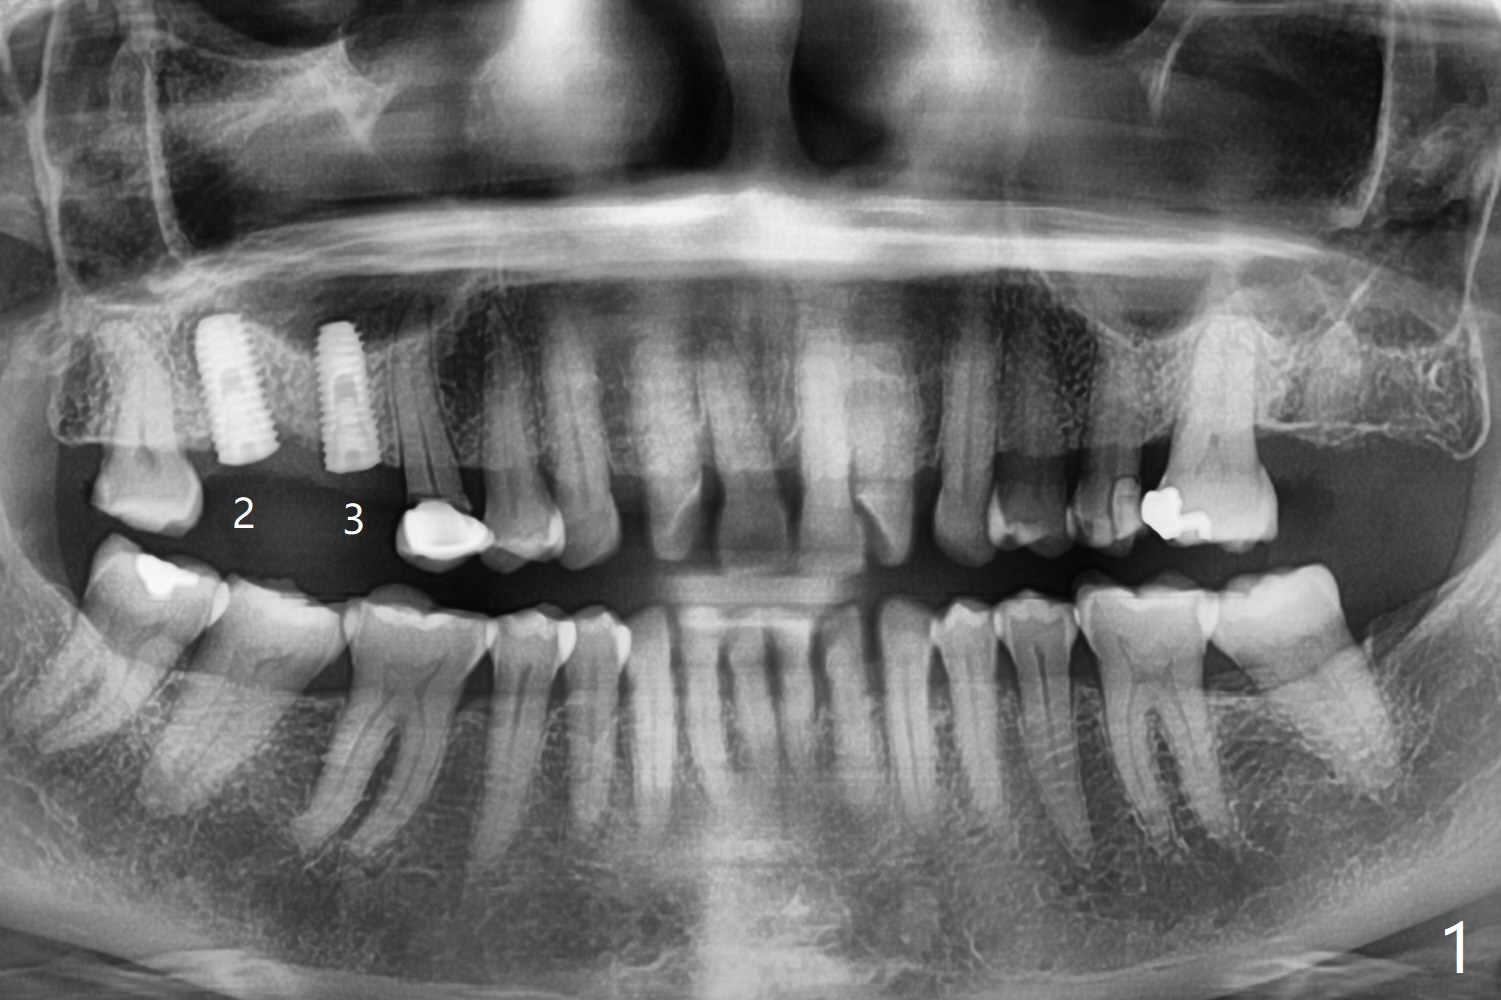

A 65-year-old woman cracks the tooth #13 (Fig.2) while the implants placed at #2 and 3 in her home country are osteointegrating (Fig.1). Extraction turns out to be surgical; after removing the curved root, the socket is large. Osteogen plug is placed for socket preservation due to finance (Fig.3 *). While the socket has healed, the buccal plate has collapsed 2 months postop (Fig.4).